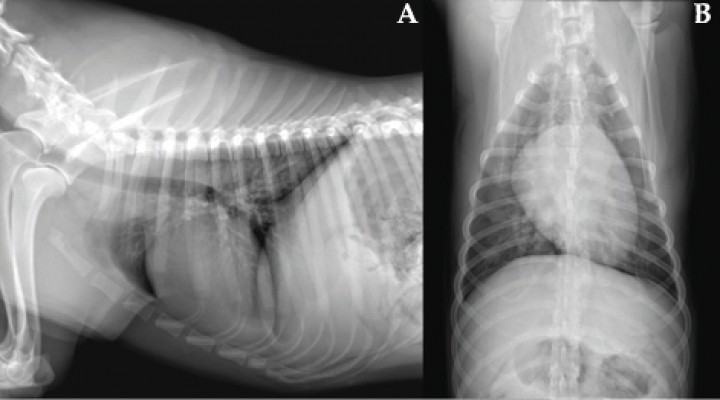

En este caso se optó por un tratamiento conservador, consiguiendo una evolución favorable, tal como se observa en las radiografías de control (Figs. 4 y 5). Aunque no se dispone de confirmación histopatológica, la evolución clínica y radiológica refuerza el diagnóstico de hematoma tímico, hemotórax y hemorragia pulmonar difusa.

<p>Radiografías realizadas a los 6 meses. (<strong>A</strong>) Proyección laterolateral derecha. (<strong>B</strong>) Proyección ventrodorsal. La resolución de los hallazgos radiográficos es completa.</p>

Radiografías realizadas a los 6 meses. (A) Proyección laterolateral derecha. (B) Proyección ventrodorsal. La resolución de los hallazgos radiográficos es completa.